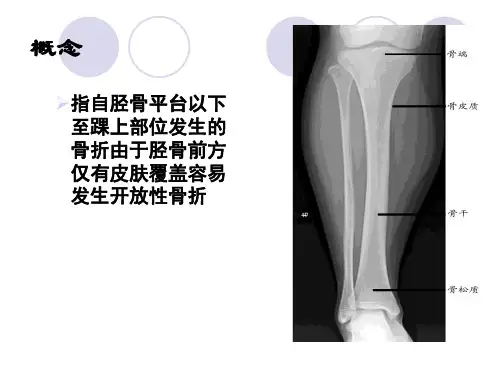

胫骨全长的内侧1/3面仅位于皮下而无肌肉组织保护,骨折易成为开放性,污染常较严重。

其前方的嵴及前内侧面从胫骨结节至内踝上仅位于皮下,易触及,而且骨质坚硬。

(图2-2-12-1)(图2-2-12-2)腓骨头及远1/3腓骨仅有皮肤覆盖,可触及。